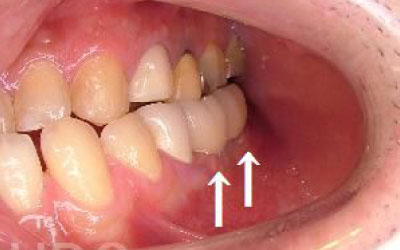

歯が抜けてそのままにしたら他の歯がズレてしまいました。どうしたらよいでしょう?

軽いズレなら調整や詰め物で対応できますが、大きく傾いた場合は矯正や被せ物が必要です。ズレが広がる前に早めの診査・治療をおすすめします。

多少の位置のズレであれば、噛み合わせの調整や小さい詰め物で調整することも出来ます。

ただ、抜けてから数年が経って大きく傾いた歯は歯並び矯正をするか、 歯を大きく削ってかぶせ物をする必要があります。

しばらくすると抜けたままでも慣れてきますが、大きな問題が発生します。

2 歯が傾いてくる、落ちてくる

歯の位置は互いに支え合ってバランスを保っています。 つまり、歯が抜けることによって支えが無くなり抜けた部分の両隣の歯が倒れたり、 上の歯が下がってきたりします。